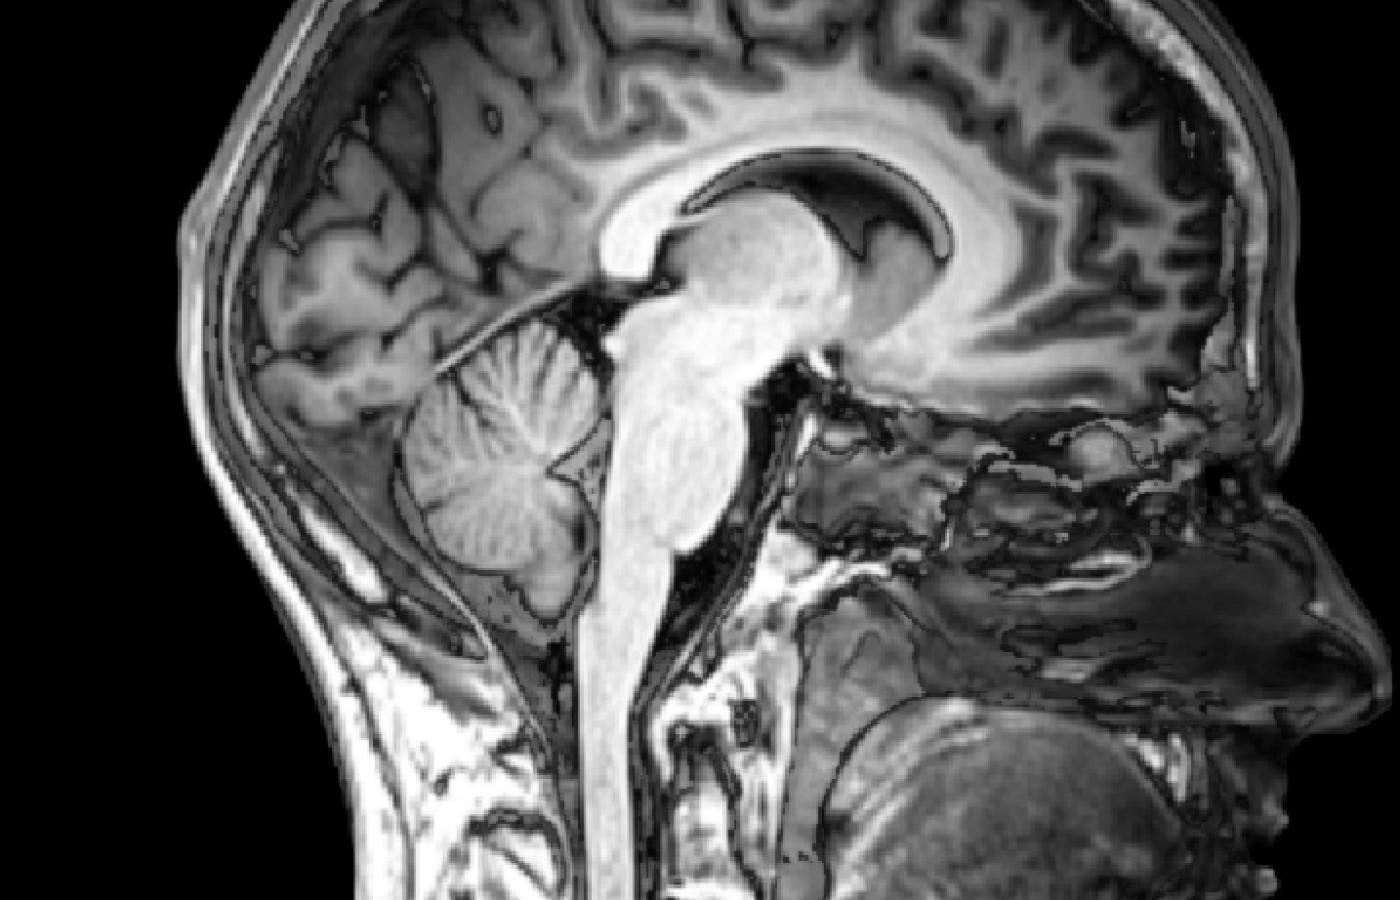

W ostatnich latach na temat funkcjonowania mózgu dowiedzieliśmy się znacznie więcej niż przez kilka poprzednich stuleci. Ale wciąż towarzyszy nam dramatyczne pytanie: czy ludzki umysł potrafi zrozumieć jak działa mózg? I czym jest świadomość?